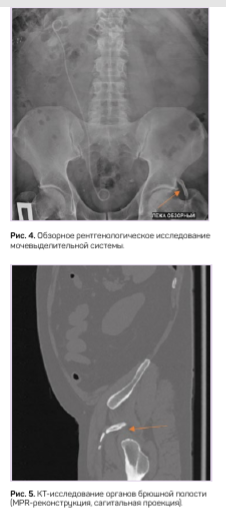

На обзорной урограмме с захватом лонного сочленения у пациента М. была обнаружена костная структура с фалангообразной перемычкой в области левого тазобедренного сустава, связанная с телом подвздошной кости (рис. 4). Эта «находка» соответствовала ранее найденному «тазовому пальцу» у пациента С. Компьютерно-томографическое исследование показало костную структуру с четким кортикальным слоем (рис. 5).

КТ — наиболее ценный диагностический инструмент, поскольку он позволил облегчить диагностику, определить количество костных сегментов и (псевдо-) сочленений, произвести точные измерения длины и обеспечить более точную трехмерную локализацию. Кроме того, это позволило оценить анатомические взаимоотношения тазового пальца с соседними мягкими тканями и суставами.